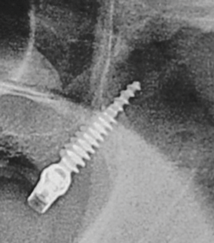

Pterygoid implants have been defined as "[an] implant placed through the maxillary tuberosity into the pterygoid plate"28 (Figure 4). Pterygoid implants cross the maxillary tuberosity from the edentulous second or third molar regions to engage the dense cortical bone formed by the posterior wall of the maxillary tuberosity, horizontal process of the palatine bone, and pterygoid process of the sphenoid bone.12,25,28

Fig 4. Radiograph showing a 3.5 mm x 20 mm pterygoid implant placed through the left maxillary tuberosity and engaging into the dense bone of the pterygoid plate.

Figure 4